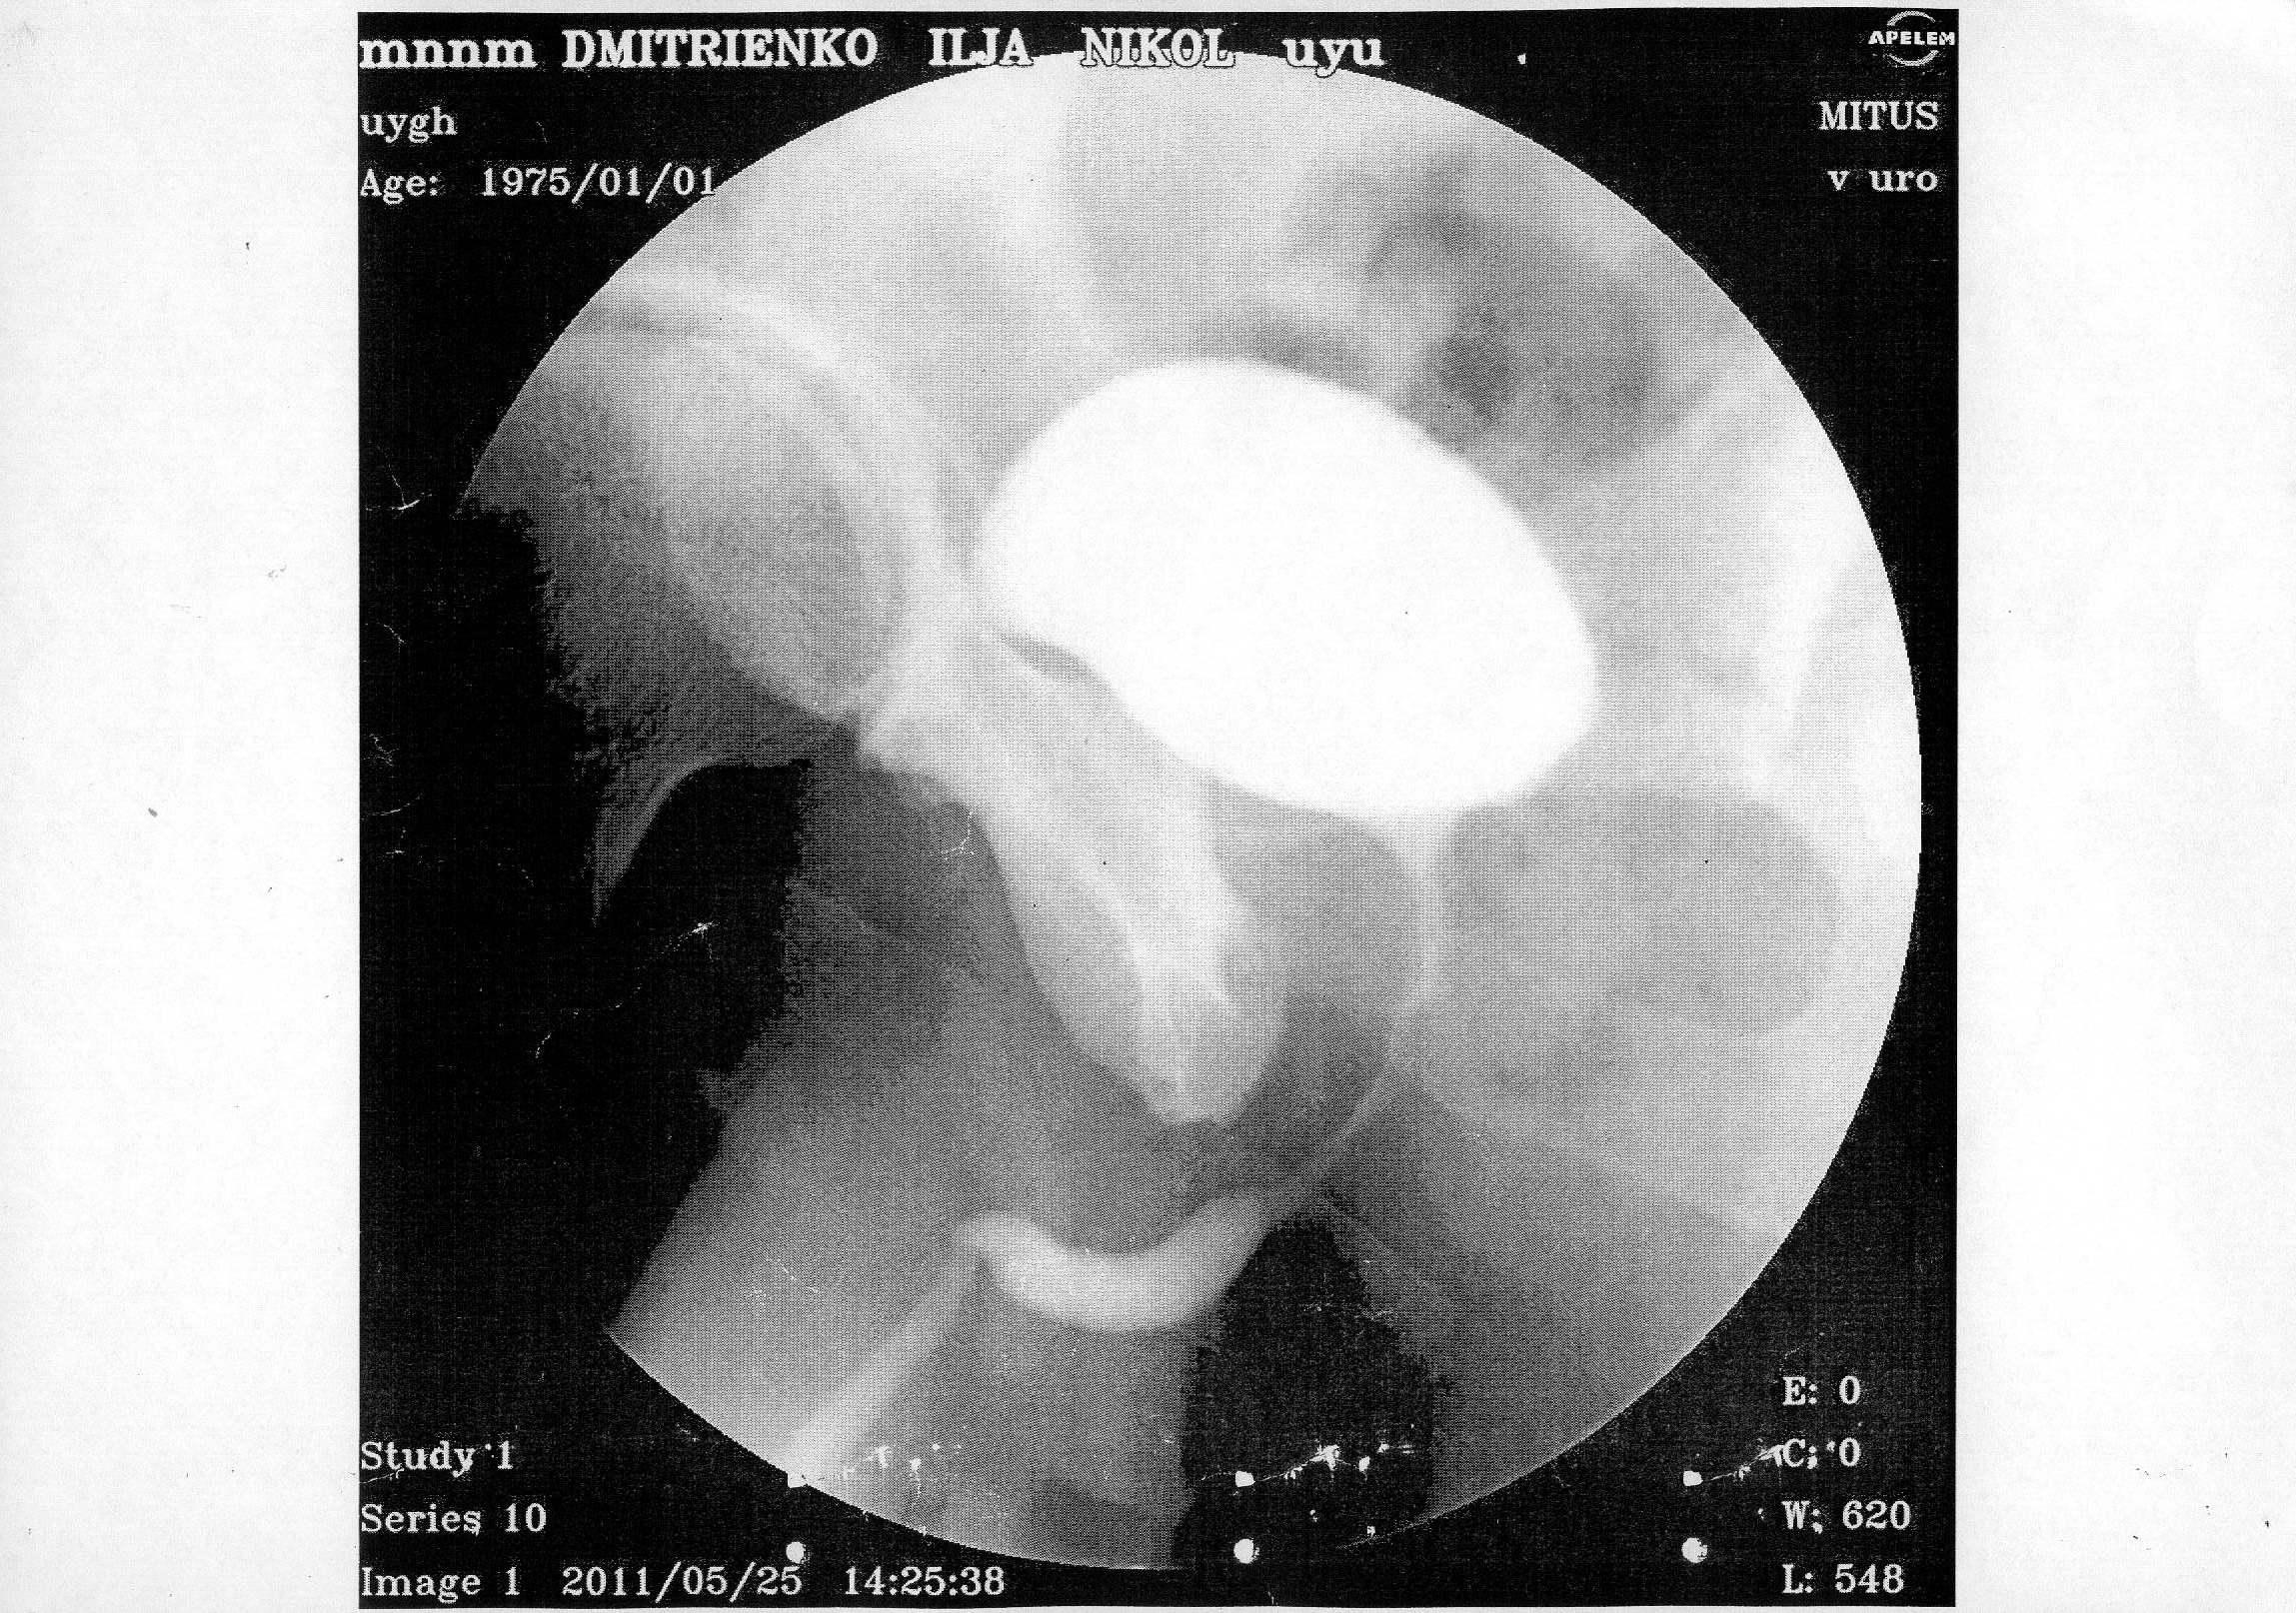

В начале 2011 года, в январе попал в , г. Алматы (был в командировке в Кзахстане)чеиспусканием, после проведенной уретроскопии, началось обострение, продержали в больнице неделю, вводили в/в антибиотики, была проведена инфузионно-детоксикационная терапия, физиолечение, делали восходящую и нисходящую уретроцистографии - б/о.

По приезду на Украину, боли не проходили в задней части уретры, было учащенное мочеиспускание, сдавал у местных урологов рахзличные анализы ПЦР на ЗППП - отрицательно, ОАМ, ОАК, различные посевы - все в пределах нормы. В конце марта сделал уже в г. Киева - КТ - на ней показало сужение простатической части уретры, было предложено бужирование, я отказался и поехал в Ростов, к профессору Когану, там провели исследования и сказали, что пока ничего не видят. Боли остаются, после полового акта боль усиливается, и учащается мочеиспускание. Не знаю, может быть болит семенной бугорок, могли задеть при уретроскопии, после которой и начались такие проблемы.